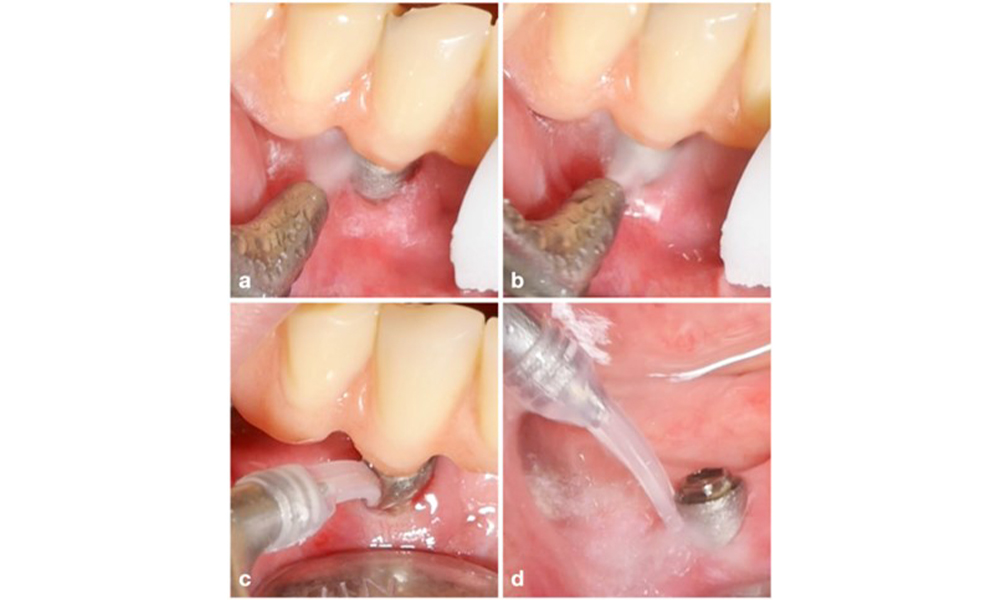

The choice of equipment depends on clinical circumstances, such as the distinction between calculus and soft plaque. Thus, in cases with calculus, titanium or plastic curettes, or specially designed tips for ultrasonic scalers should be used first, followed by the use of an air-polishing device (figure 7). In cases with only soft plaque accumulation, an air-polishing device alone can be sufficient. Air-polishing devices are operator and patient friendly and at least as efficient as standard instruments (Schwarz et al. 2015a).